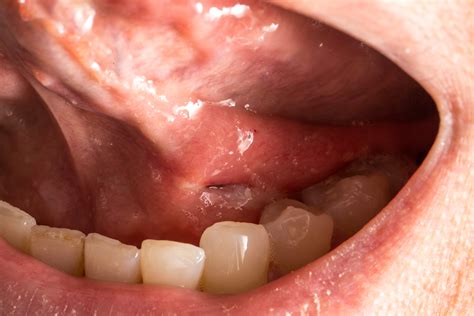

Reconstructive Dental Options After Oral Cancer Surgery

Reconstructive Dental Options After Oral Cancer Surgery

Oral Cancer Screening - Gentle Dentistry of Poway, CA

Oral Cancer Screening - Gentle Dentistry of Poway, CA